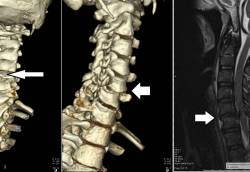

神经系统:当神经受到压迫时,神经纤维的轴浆运输流动受阻碍,继而引起手麻。从颈部椎管出发到手掌的神经主要有桡神经、尺神经、正中神经,穿过关节、韧带、骨纤维管到达手掌末梢,在任何一个部位,神经受到压迫,都可以引起手麻。